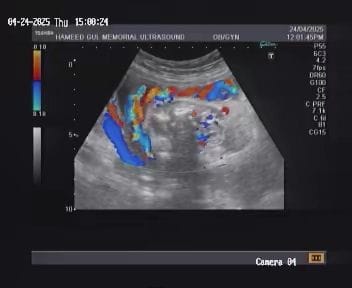

doppler imagies

Doppler ultrasound provides critical information about the blood flow within vessels and tissues, enabling precise diagnosis of vascular conditions.